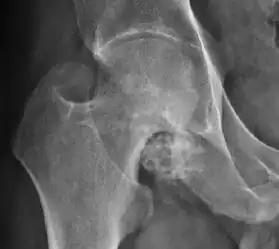

- Osteoarthritis

In adults, one of the main indications for radiographs is the detection of osteoarthritic changes (Figure 1(e)). Nevertheless, radiographs usually detect advanced osteoarthritis that can be graded according to the Tönnis classifications. The grading system ranges from 0 to 3, where 0 shows no sign of osteoarthritis. Intermediate grade 1 shows mild sclerosis of the head and acetabulum, slight joint space narrowing, and marginal osteophyte lipping. Grade 2 presents with small cysts in the femoral head or acetabulum, moderate joint space narrowing, and moderate loss of sphericity of the femoral head. Grade 3 is the severest form of osteoarthritis, which manifests as severe narrowing of the joint space, large subchondral cyst with productive bone changes that may lead to deformity of the bone components of the joint, while secondary osteoarthritis due to calcium pyrophosphate deposition can be diagnosed when calcification of hyaline cartilage and fibrocartilage is detected.[1]

There are other pathological conditions that can affect the hip joint and radiographs help to make the appropriate diagnosis. Acute bacterial septic arthritis can be diagnosed by radiographs when a fast regional osteoporosis and destructive monoarticular process develops (Figure 1(f)). In case of tuberculous or brucella arthritis it is manifested as a slow progressive process, and diagnosis may be delayed.[1]

Plain radiography allows us to categorize the hip as normal or dysplastic or with impingement signs (pincer, cam, or a combination of both). Besides these, pathologic processes like osteoarthritis, inflammatory diseases, infection, or tumors can also be identified (Figure 1).[1]